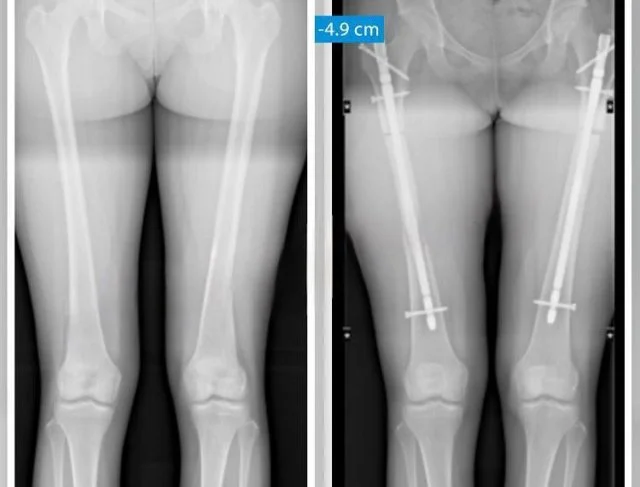

Хирурги спиливают часть бедренной или большеберцовой кости, уменьшая рост на 3–5,5 см. Например, одна пациентка снизила свой рост с 172 до 167 см.